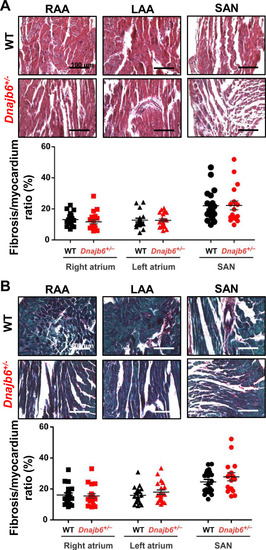

Fibrotic tissue content in atrial and SAN myocardium of Dnajb6+/-vs.WT mice. (A–B) Masson’s Trichrome (A) and Picrosirius Red (B) staining of WT and Dnajb6+/- mice are shown for left (LAA) and right (RAA) atrial appendages as well as SAN regions. Below the representative images, summarized data for fibrotic to myocardial tissue ratio are shown for each staining. N=4 mice per group. Scale bars, 100 µm. |